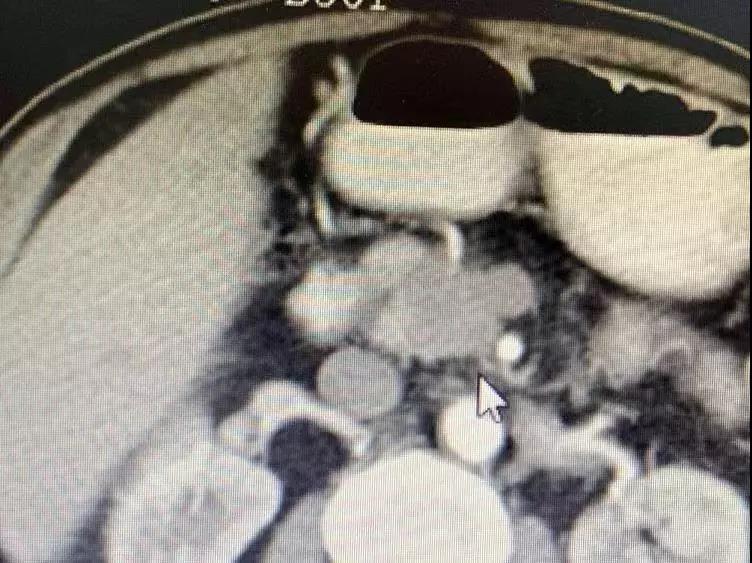

胰腺肿瘤包绕血管,及腹腔淋巴节转移

通过护士了解到,梭和梭的家属都很亲切,打招呼时候总会双手合十放在胸前向你微笑点头,说话也很温和。梭生活在印度教和佛教浓厚的尼泊尔里,连耳垂都与佛有几分相像。梭是今年四月份突发上腹疼痛,五月中旬在当地医院检查发现,“胰腺钩突肿物,有大概3cm大小,肿块邻近肠系膜上静脉”,疑是胰腺癌。在7月25号再次检查发现,病情严重了,出现“侵及肠系膜上静脉及肠系膜上动脉;腔静脉前及主动脉旁多发小淋巴结”;由于医疗条件有限,没有很好的治疗方案。他的医生拉吉夫向他介绍了中国的肿瘤医院。

为了早一点治疗父亲的疾病,梭的儿子急忙的带着他在8月31号来到复大肿瘤医院。经过多次详细检查,诊断为:胰腺癌钩突部腺癌III期和2型糖尿病。肝、肺、甲状腺等多处出现结节,需要随后跟进治疗;牛立志博士与多名医生针对梭的病情展开讨论以及跟家属沟通后,分别在9月6号行“锁骨下静脉置管术”;9月7号行“胰腺肿瘤不可逆电穿孔术”。术后经过一系列的护理,梭的情况逐渐转好。